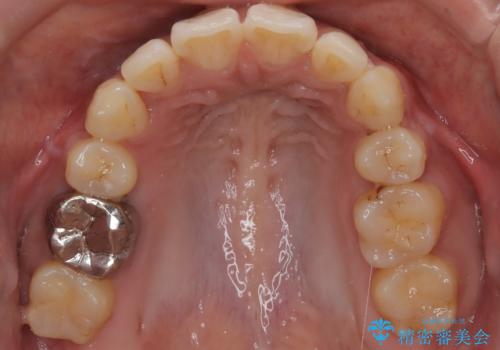

前歯の前突と口元の突出感を改善|上下左右4番抜歯+審美ワイヤー矯正

- 前歯の突出が強く、口元が前に出ている印象を改善するため、上下左右の第一小臼歯(4番)を抜歯する矯正治療を計画しました。抜歯により得られたスペースを利用して、前歯を後方へと移動させて整列します。治療には目立ちにくい透明な審美ブラケットとワイヤーを使用し、毎月1回の調整を行いながら徐々に歯を動かし、約2年で口元全体を整える計画としました。

前歯が前に出ているため口元が突出し、唇が閉じにくいなどの悩みを抱えておられました。治療にあたり上下左右の第一小臼歯を抜歯し、十分なスペースを作ることで前歯を効果的に後方へ移動させました。装置には透明で目立ちにくい審美ブラケットを採用し、治療中の審美的ストレスを軽減しました。定期的な調整を通じて無理なく確実に歯列を整え、前歯の突出感を解消。治療後は口元の印象が自然で美しく改善され、患者様には非常にご満足いただけました。